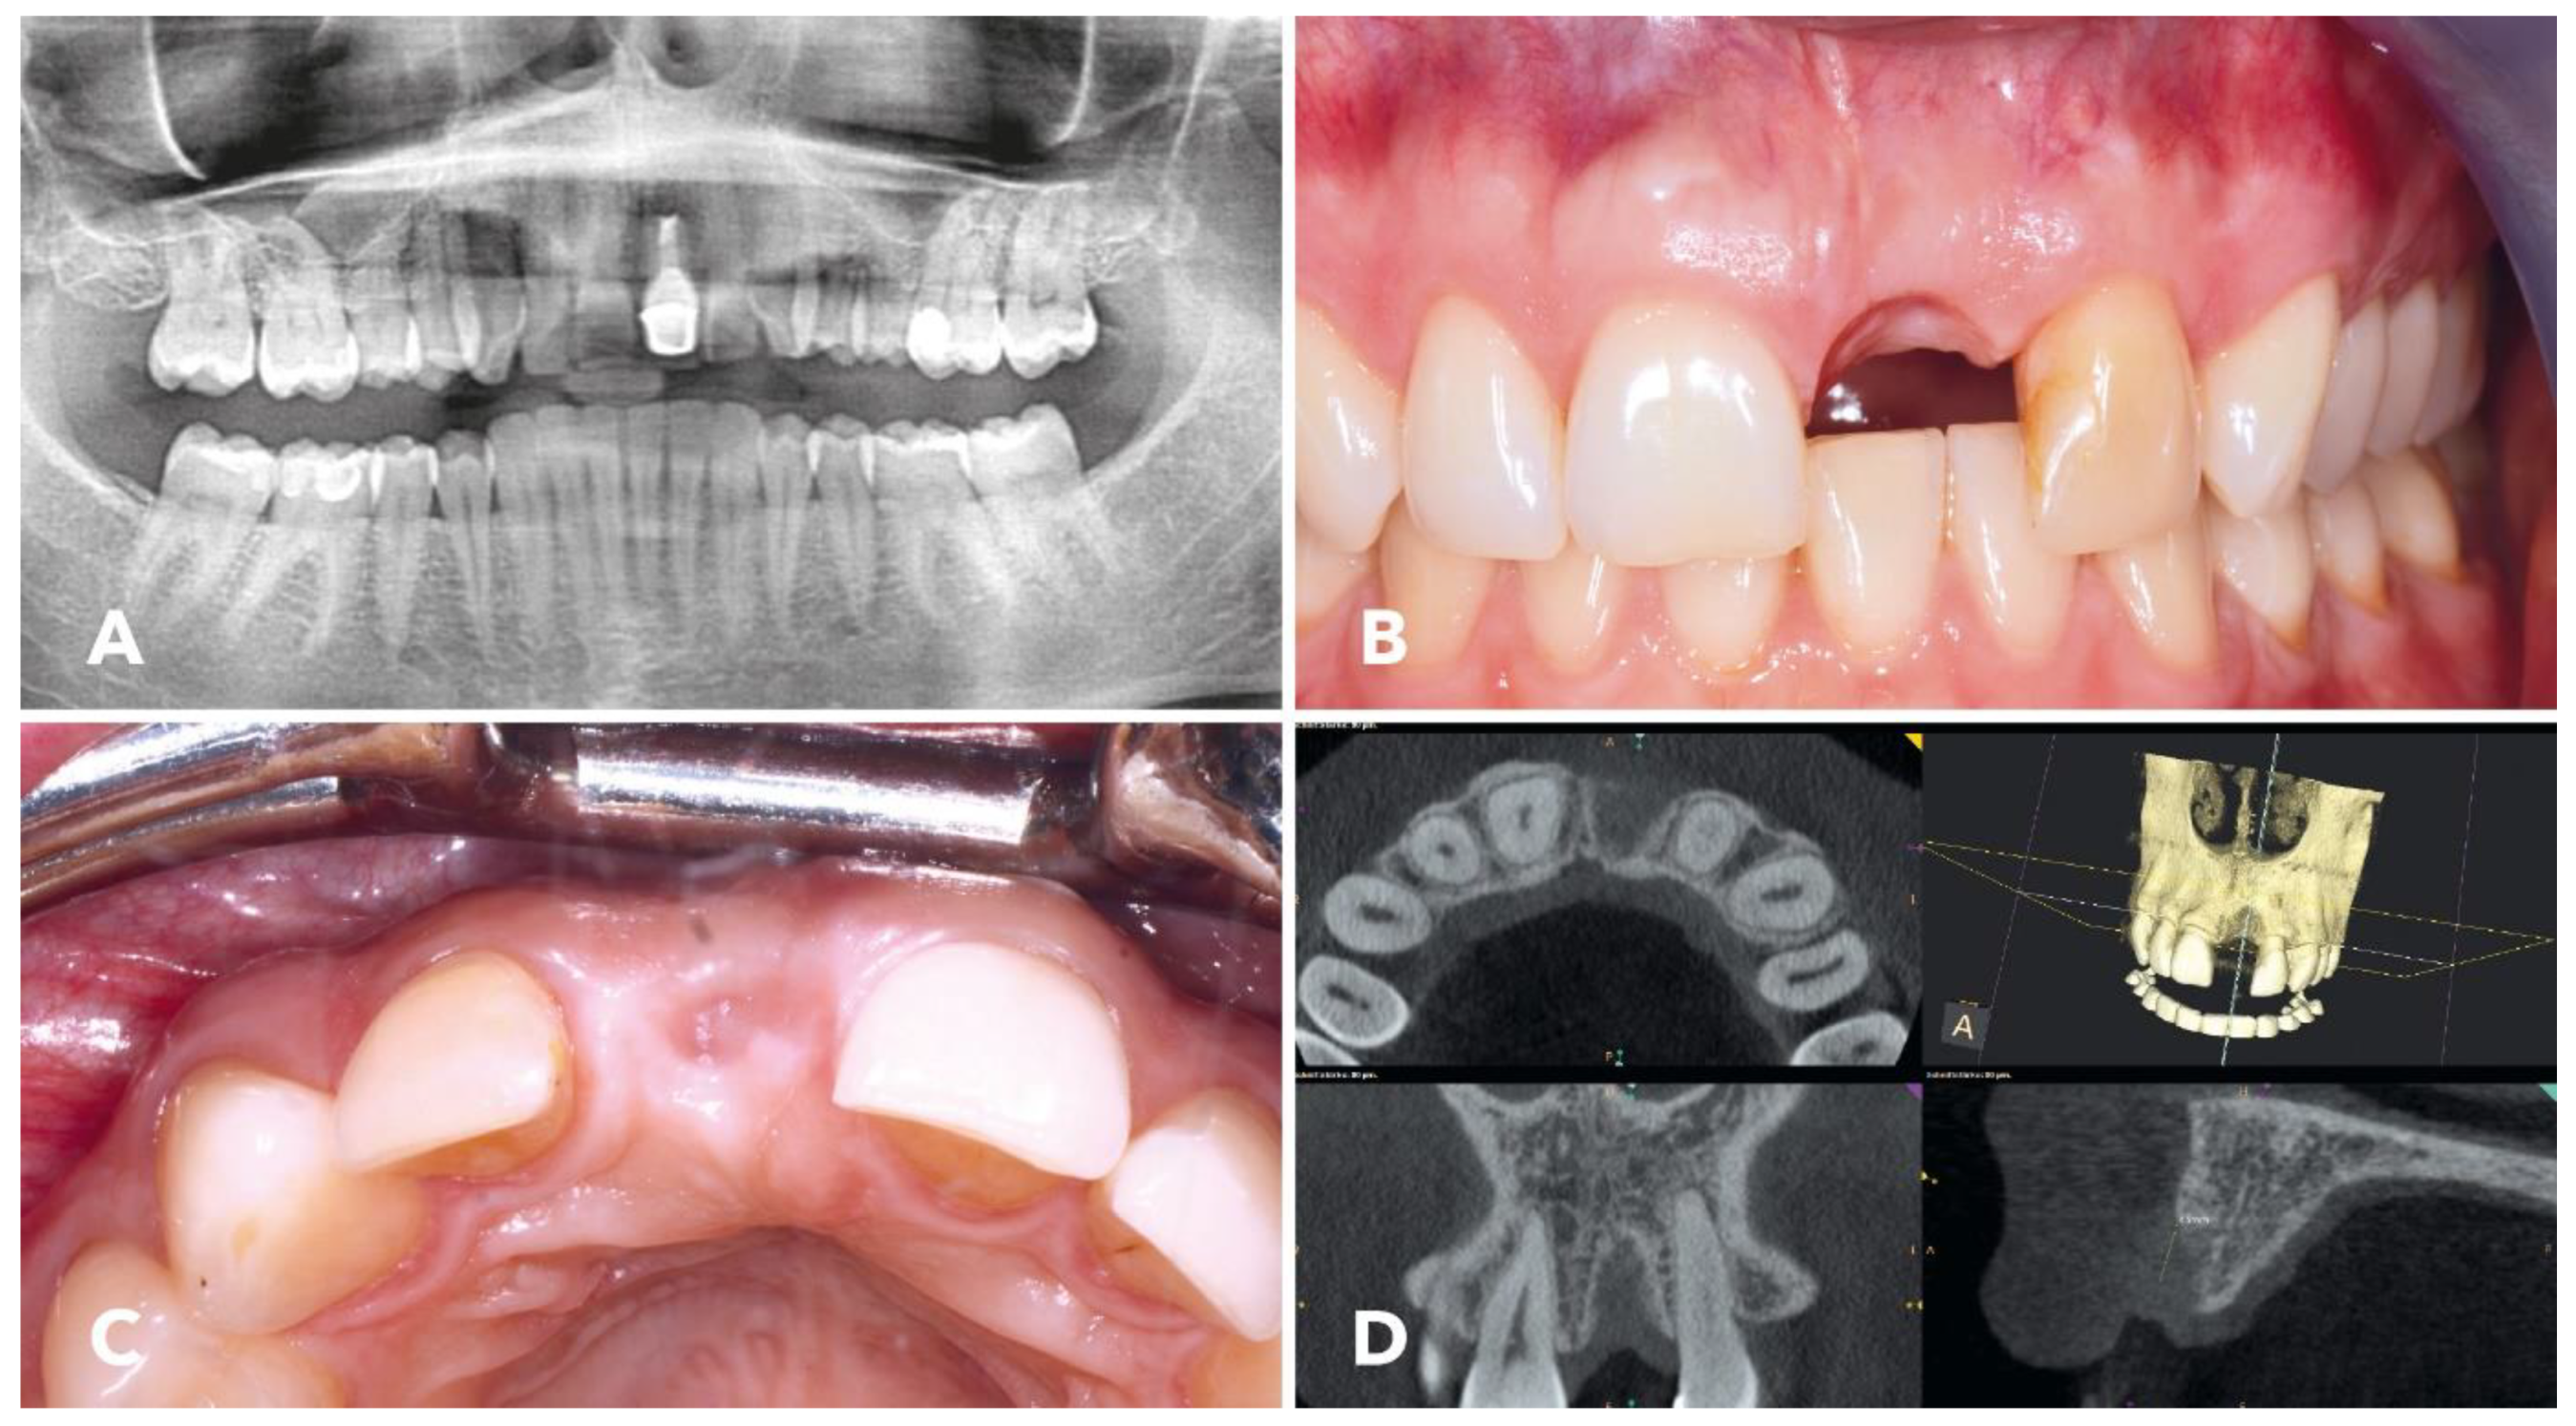

2.1. Overview of the Clinical Case

2.4. Surgical Procedure